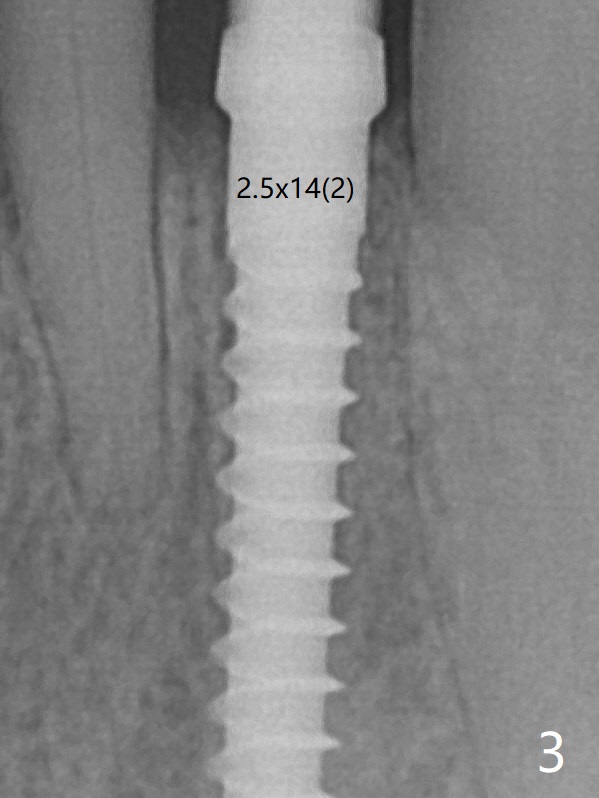

The gingival depth is measured 2-4 mm after extraction. The 1st intraop PA taken with 1.2 mm drill for 16 mm shows the mesiodistal width is 5.11 mm (Fig.2); a 2.5x14(2) mm 1-piece implant is placed with >35 Ncm (Fig.3 with allograft placed). There is no bone loss 3 months postop (Fig.5). The distal crest seems to be reduced in density and lower in height 1 year 7 months (Fig.7) and 1 year 11 months (Fig.8) post cementation. The severity does not worsen probably related to use of water pik.